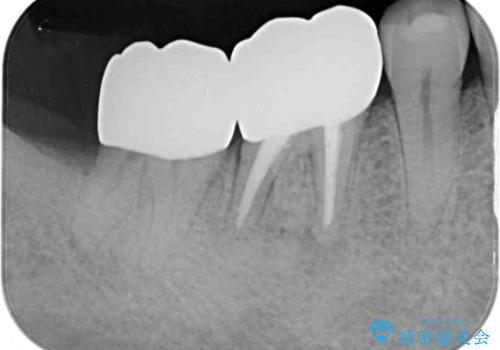

- 親知らずを抜くことが怖く、先送りにした結果親知らずの前の歯に大きな虫歯ができてしまったとのことで来院された患者様です。

親知らずは速やかに抜歯し、手前の歯とその前の歯に歯槽骨にまで及んだ虫歯が認められたため、歯槽骨を削るなどの歯周外科処置を行うこととしました。

外科処置後の経過を待って、フルジルコニアクラウンにて補綴することとしました。